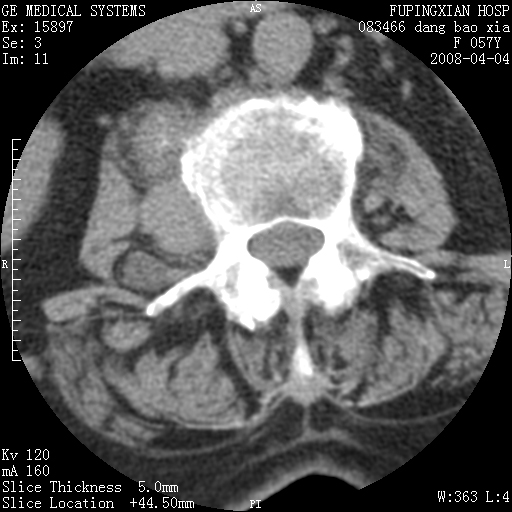

标题: CT12677:女性,57岁,疼痛数月。 [打印本页]

标题: CT12677:女性,57岁,疼痛数月。

椎体及附件骨质破坏同时伴软组织肿块,首先考虑恶性肿瘤。

病灶见多部位;转移瘤

查原发灶吧,考虑转移瘤。老年人出现骨肿瘤首先要除外转移瘤及骨髓瘤。

椎体及附件溶骨性破坏,周围巨大软组织肿块,首先考虑转移瘤。